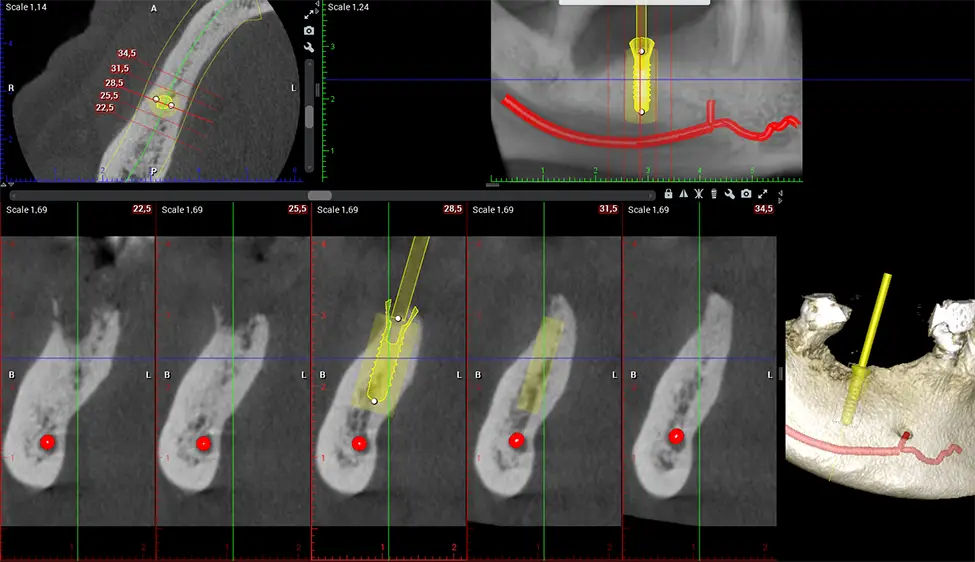

Cone Beam Computed Tomography (CBCT) is an advanced imaging technique used in dentistry and maxillofacial surgery to obtain detailed 3D images of the oral and maxillofacial structures. At Dr G Dental Studio, our CBCT scanners utilize a cone-shaped X-ray beam and a specialized detector to capture images from different angles. A computer then combines these images to create a 3D representation of the patient’s oral anatomy.

After the scanning process, the captured X-ray images are processed by the CBCT software, which applies algorithms to reconstruct a detailed 3D image of the scanned area. The software compiles these individual X-ray images and creates a digital 3D representation of the patient’s anatomy. The reconstructed 3D CBCT image can be viewed and analyzed by the dentist or radiologist. This image can be manipulated, rotated, and zoomed in or out to examine specific structures and evaluate the patient’s condition.

Oral and Maxillofacial Surgeon Complex oral surgeries, orthognathic (jaw) surgery, and removal of impacted teeth. Offers precise, three-dimensional visualization of the skull, jaw, and craniocervical junction to enhance diagnostic accuracy and minimize surgical risks.